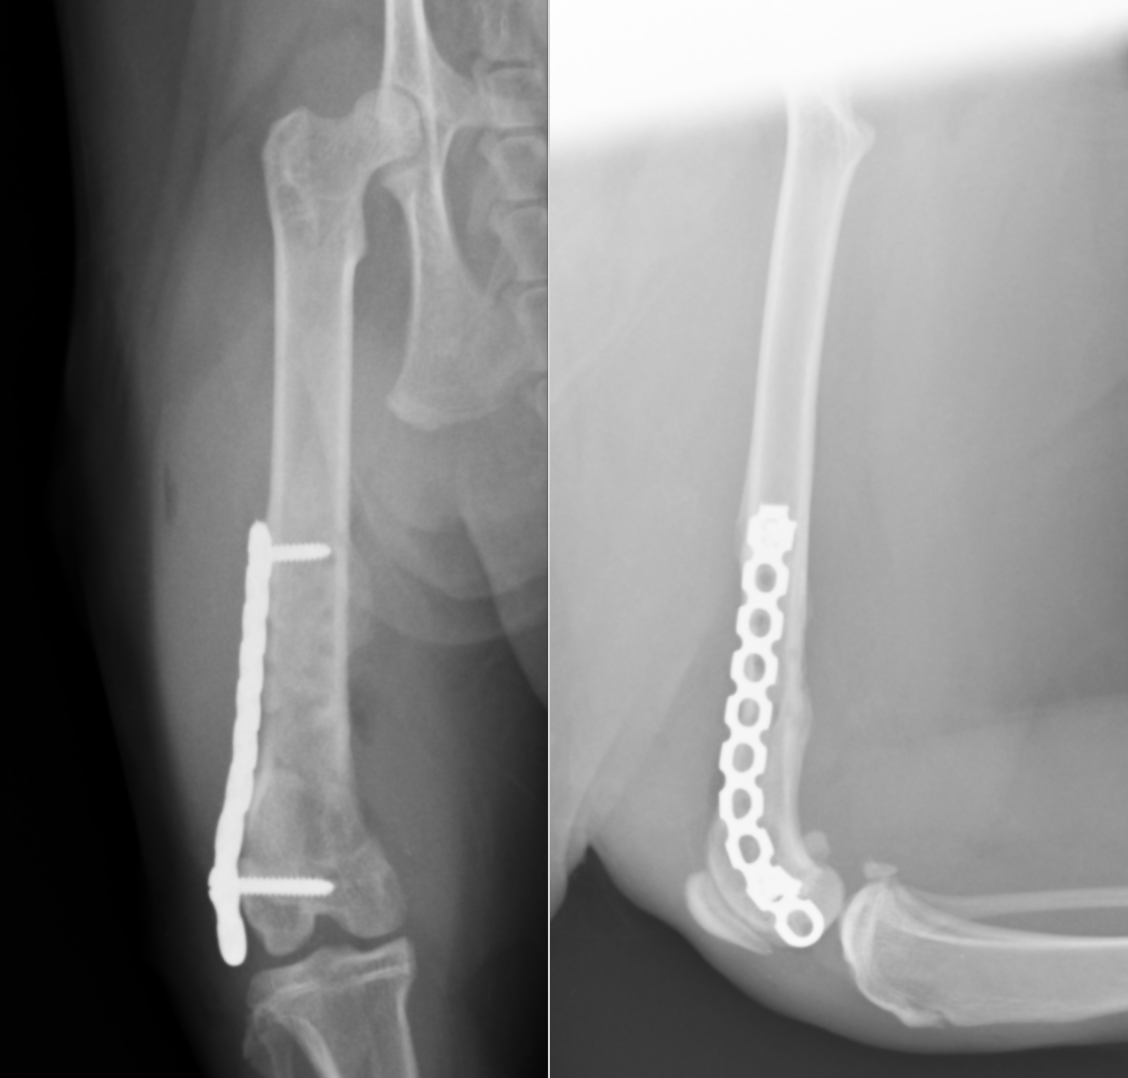

術後のレントゲンです。髄内ピンとして長いピンが2本と、外側にLCPというプレートと、ロッキングスクリュー、内側にリコンストラクションプレートと、コーテックススクリューが設置されています。

今回は術後2ヶ月ほどでプレートとピンを一部抜去しインプラントの強度を弱めました。ココまでくればもう通常通りの生活に戻ることが可能です。